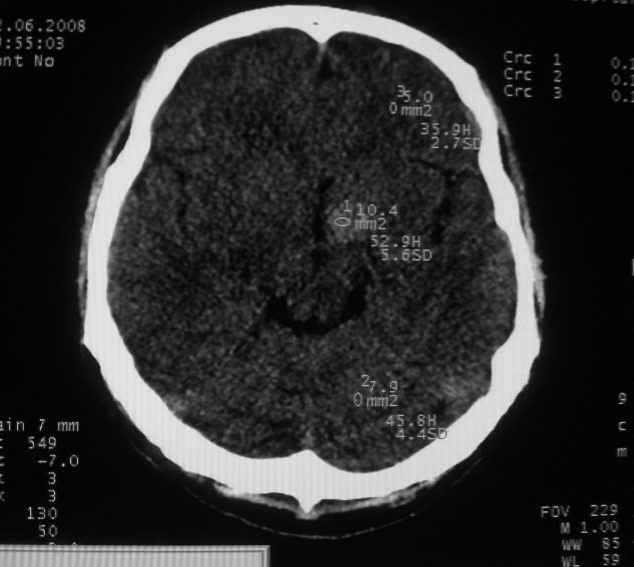

以下是引用守望可可西里在2008-6-13 1:25:00的发言:[br][br] 1.双侧大脑中动脉高密度踌型样接近于全程显示,部分大脑前动脉、基底动脉也呈高密度改变。[br] 2.右侧基底节多发类圆形ct值接近于出血的高密度,边缘模糊。双侧小脑幕及直窦、上矢状窦增宽、模糊。左侧横窦和乙状窦区密度增高、呈云雾状,内缘模糊。[br] 如果这样的表现发生在一个老年人脑部,我们首先会想到是高血压、动脉粥样硬化,就可以很容易得出结论。但这发生在一个20岁年青人的身上,且病程长达半年、临床症状不怎么重,这就比较蹊跷且应该引起高度重视了。[br] 我认为此病人应该是一个血液病患者--双侧大脑中动脉、部分大脑前动脉及基底动脉的高密度改变,只是一个假象:即相对于ct值偏低,只有35的脑灰质而言的相对高密度。而那么多出血改变,则是真正的病变表现。[br] 建议临床进一步进行其他相关的血液、骨髓检查,肝、脾也应该好好检查,应有明显的肿大。